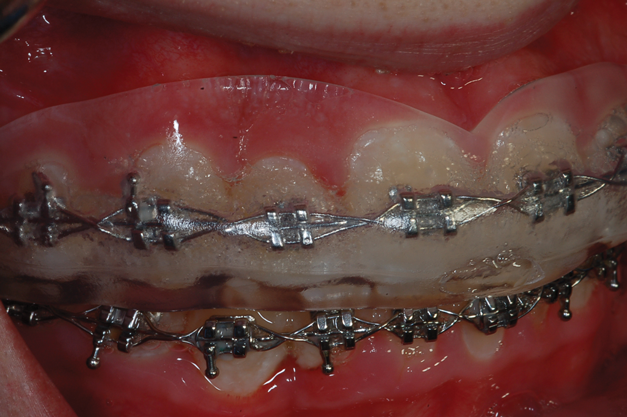

One of the biggest challenges for teenagers wearing braces is the time that it takes for proper oral hygiene to avoid white spot lesions and active caries.12 Furthermore, their eating habits and lifestyle do not always support good hygiene practices. Research indicates that the use of 10% carbamide peroxide for bleaching results in a reduction of caries because it creates a more basic oral environment with a pH greater than 8.0 within 5 minutes after insertion,13 removing plaque and killing bacteria that cause tooth decay.14 Therefore, tray application of carbamide peroxide has been recommended for elderly and special needs patients with root caries when fluoride trays are ineffective.2,15 It can also provide caries control benefits for patients with orthodontia.

For orthodontic patients, the single clear tray used is 1.5-mm thick. Due to its thickness and the presence of the orthodontic brackets, the dentist takes a more active role in molding this clear tray intraorally. The tray is heated in the same manner as the previously discussed thermoplastic trays. Even when completely softened, it will not become imbedded into the brackets. When seating it, the path of insertion into the mouth should be slightly more facial to avoid engaging the tray edges on the brackets. The dentist must act quickly to seat the tray intraorally and begin applying pressure on the walls from the anterior to the posterior segments to adapt the tray over the brackets and onto the gingiva before it cools. As before, the patient will bite on his or her back teeth and produce suction to create a vacuum. When the tray has lost its heat, it is removed from the mouth, and the handle is removed with crown and bridge scissors. The patient or dentist may initially experience difficulty in determining the seat of the tray because the tooth molds are not as pronounced due to the presence of the orthodontic appliance. However, the tray will have a definite seat and fit once the path of insertion is found, and the patient should be able to insert and remove it easily (Figure 9).

For bleaching treatment, the carbamide peroxide is injected into the tray via the trough created by the arch wires and brackets, and then the tray is inserted into the mouth. Typically, more bleaching material is used with this treatment in order to fully penetrate the wires and brackets to mechanically and chemically clean the braces (Figure 10). It is recommended that patients wear the tray while sleeping because of the reduction in saliva flow that happens nocturnally. A new tray will need to be made about every 3 to 4 months due to the shifting of the teeth, but this soft tray will not impede the progress of the orthodontics. The tray is difficult to fabricate on the mandibular arch because it requires good tongue control by the patient to be successful. Although a conventional alginate impression could be made, it would require removing the arch wires each time, and it would not capture the gingiva as well as a tray made directly in the mouth.

Another preventive option involves injecting carbamide peroxide directly onto the braces prior to brushing (Figure 11), which immediately causes a foaming, bubbling action when the material comes into contact with plaque (Figure 12). The use of this approach to chemically clean the braces as well as the use of 3% over-the-counter hydrogen peroxide in a 1:1 ratio in a water pick is beneficial to preventing white spot lesions. The only side effect of using 10% carbamide peroxide with tray treatment for caries control is that the teeth will be bleached. This is generally a beneficial coincident with orthodontic treatment and can serve as a motivator for a teenager to wear the tray. The cost of this tray bleaching treatment is approximately $400 to $600 over the course of 2 to 3 years of orthodontic treatment, which is far less than the cost of multiple composite restorations should caries occur. Any concerns that there may be yellow spots on the bleached teeth after removal of the brackets are unfounded because the material penetrates the tooth structure to bleach under existing restorations and brackets (Figure 13 and Figure 14).16

(13.) Retracted view of a patient who had been using tray application of 10% carbamide peroxide for over a year to clean the braces as well as bleach the teeth.

Figure 13